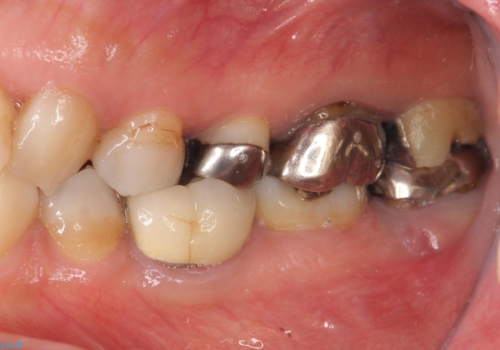

- 左下奥歯の咬合時疼痛を訴えて来院されました。

最後方臼歯周囲には大きな透過像が見られ、破折が強く疑われること抜歯が想定されることを理解していただき銀歯を除去したところ破折が認められたため抜歯を行いました。

今後の機能回復方法としてインプラント治療を希望されたため、将来的に大規模な骨造成が必要とならないよう歯槽堤保存術を抜歯と同時に行いました。

良好なインプラントの植立を行うためには、十分な骨量があることが必須条件です。

術前、歯の破折により大きな骨の吸収が認められていたため骨量を十分に回復するために抜歯と同時に歯槽堤保存術を行い十分な骨量の回復をすることができました。